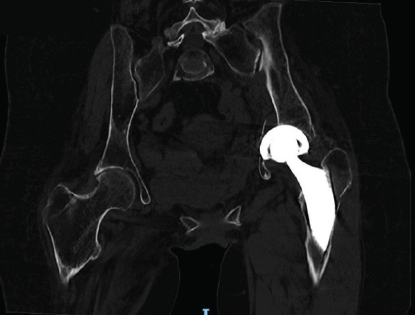

Radiographic evaluation, including computed tomography, revealed the protrusion of the acetabular cup into the pelvis, associated with a transverse acetabular fracture and a Vancouver AG-type fracture (Figs. 1 and 2).

Figure 2: Pre-operative pelvis computed tomography scan.